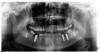

Таня@ Опубликовано 30 августа, 2009 Автор Поделиться Опубликовано 30 августа, 2009 (изменено) 1) Возможно;2) На снимках виден. замечательно!!!! а покажите пожалуйста где он вот на этом снимке?и может ли доктор поставить костный блок и не сказать об этом пациенту? и откуда кость для блока берут если делают одновременно с постановкой импланта? Изменено 30 августа, 2009 пользователем Таня@ Ссылка на комментарий

Sahan Опубликовано 30 августа, 2009 Поделиться Опубликовано 30 августа, 2009 замечательно!!!!На этом снимке я блока не вижу, но при горизонтальной аугментации в данной проэкции снимка вы блок редко сможете увидеть. Костный материал не обязательно берут у пациента, он может быть аллогенный- то есть взятый у другого человека , ксеногенный- взятый у животных и синтетический. Что использовали в вашем случае вам должны были сообщить. Ссылка на комментарий